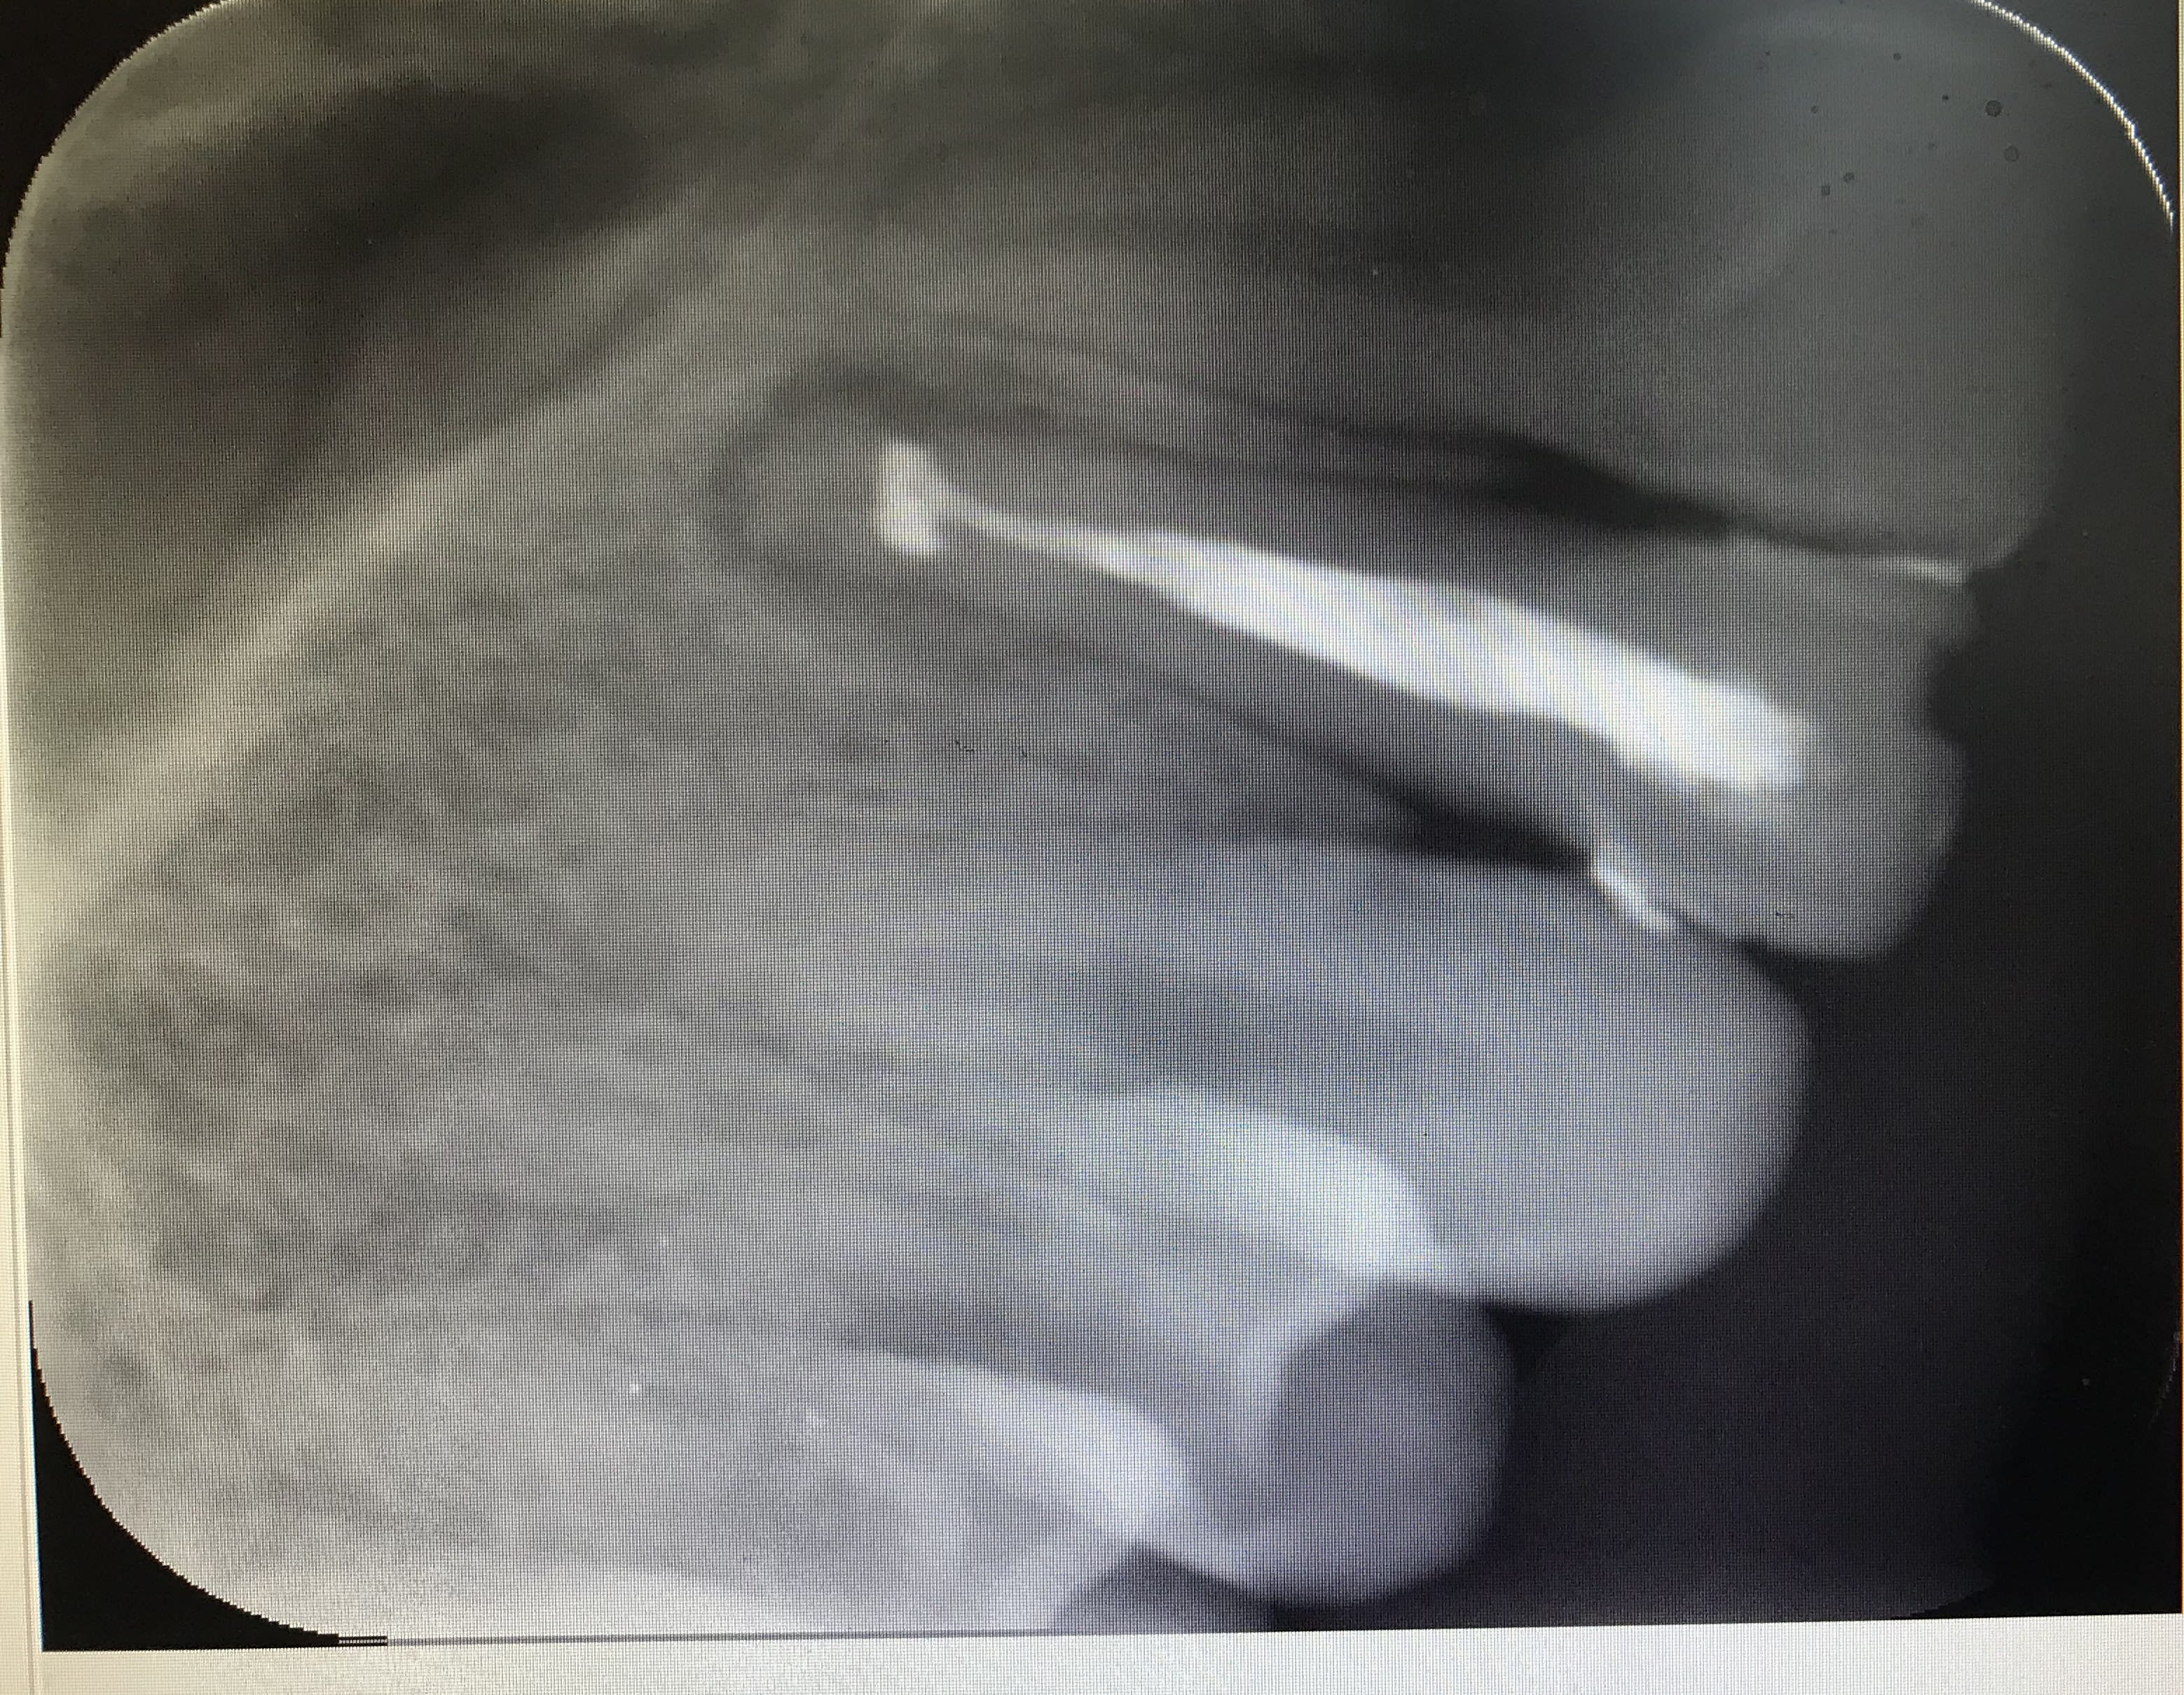

Sinon Je viens de mettre au point l’obturation horizontale à chaud :) :